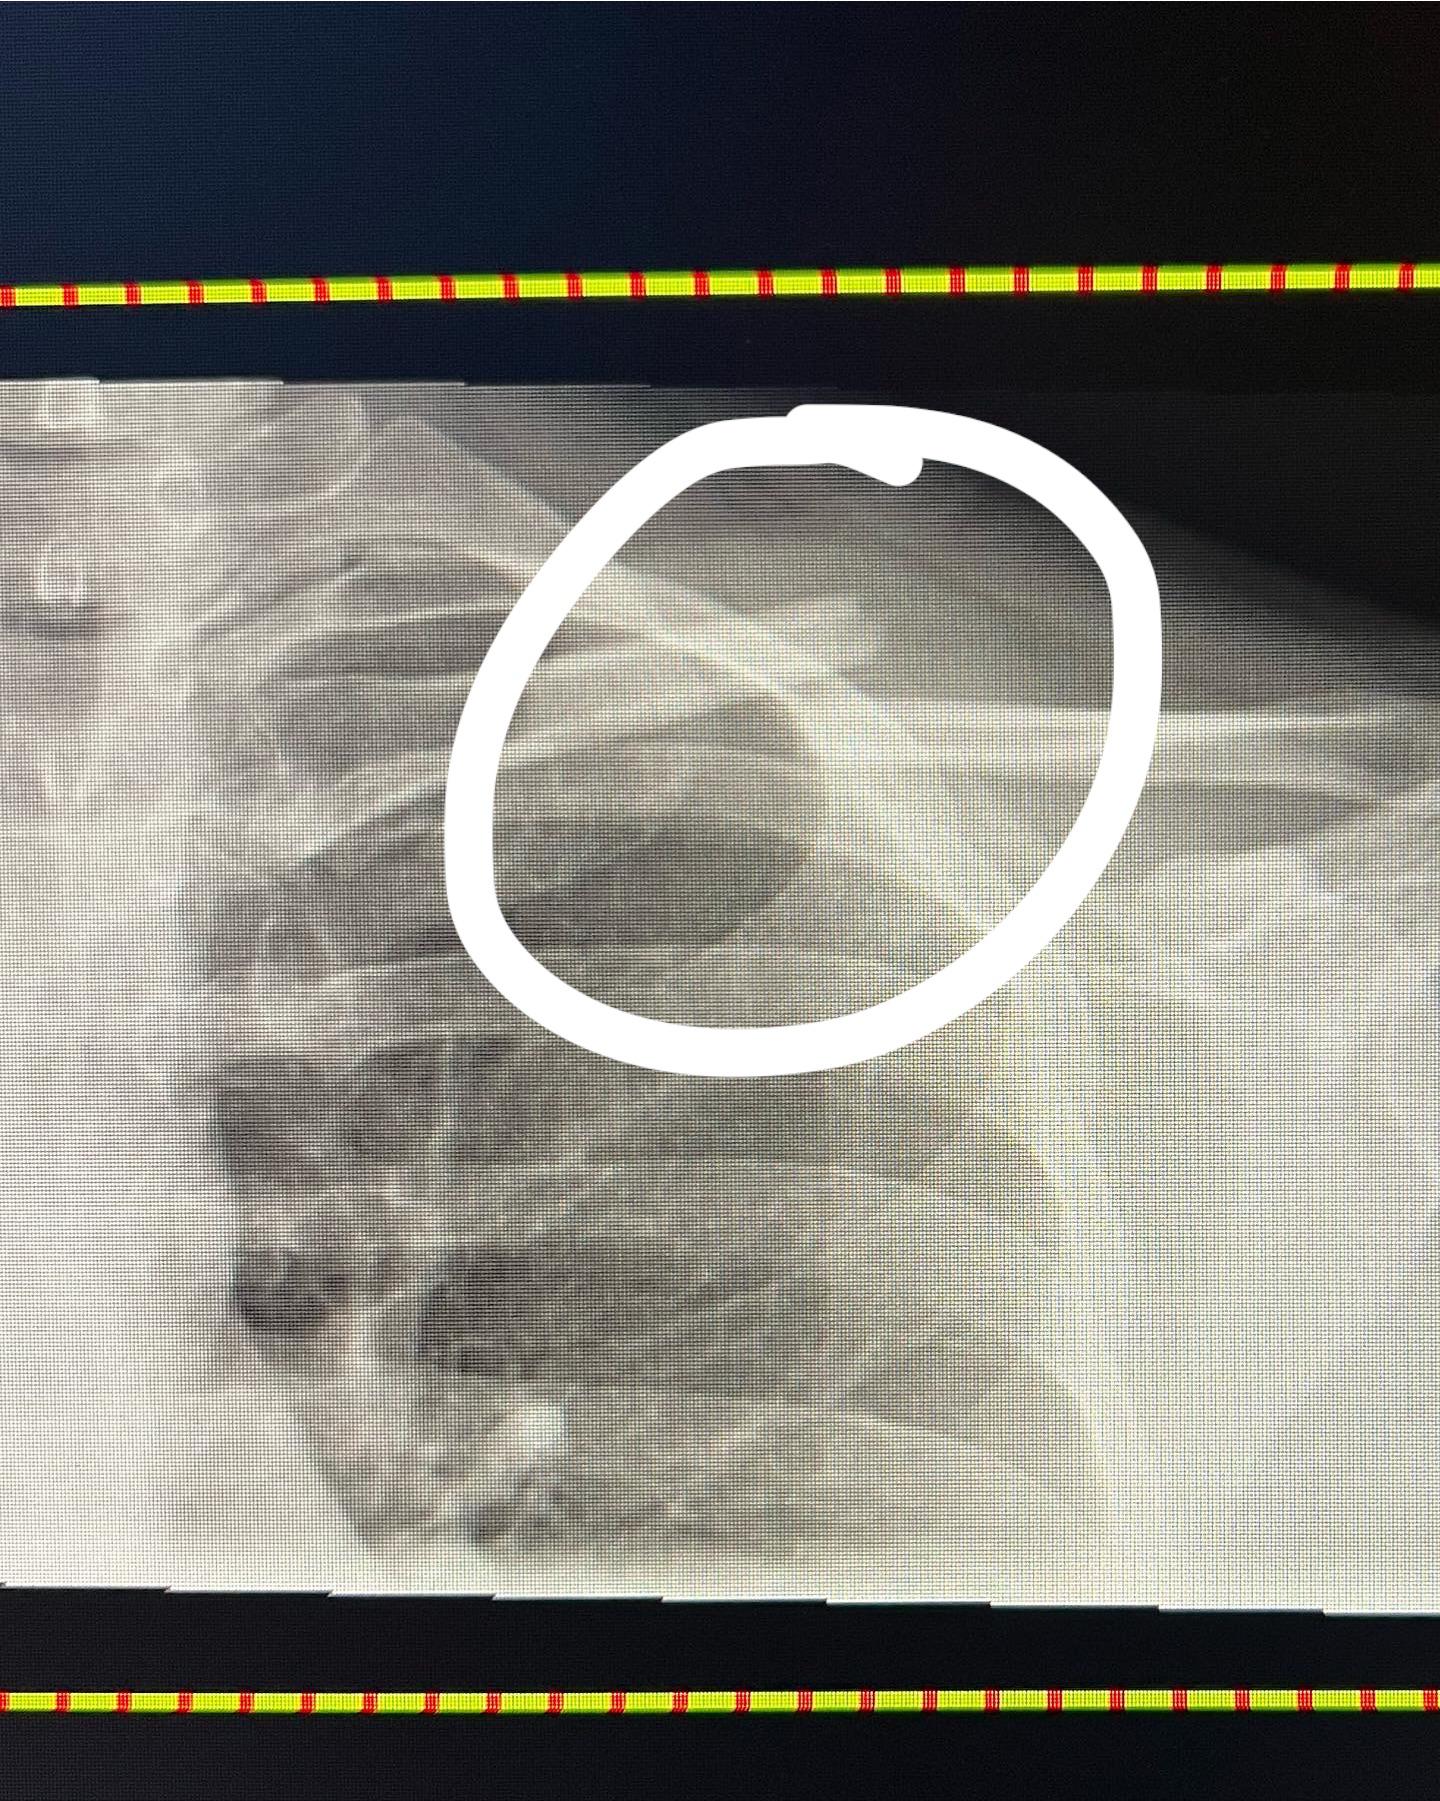

From www.reddit.com

Does this collarbone fracture look like it will need surgery?? r/medical How Much Does Collarbone Surgery Cost Ac joint surgery costs can range between $5,000 and $9,000, depending on the type of surgery, inclusion of ligament repair, and costs. How much does a knee replacement cost in singapore? Learn about the causes, symptoms, and treatment options for clavicle fractures, or broken collarbones. Knee replacements in singapore public hospitals cost an average of $5,000 to $7,000 for subsidised. How Much Does Collarbone Surgery Cost.